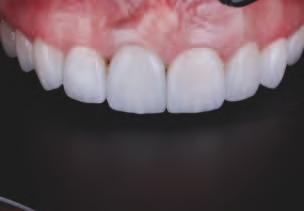

6. Configurația nouă a restaurării creată folosind modulul de proteză CAD pe baza datelor colectate din supraproteza existentă. În aceast etapă, s-au modificat dimensiunea dinților și expunerea gingivală pentru a îmbunătăți estetica.

15. Vedere extraorală a restaurărilor finale livrate.

16. Vedere intraorală a restaurărilor finale mandibulare livrate.

În cab net, restaurăr le prov zor au fost deșurubate ș îndepărtate d n cav tatea orală pentru ca restaurăr le f nale să poată f l vrate ș strânse cu un cuplu de 15 Ncm, conform recomandăr producătorulu (f g. 15,16). Ajustăr le ocluzale f nale au fost m n me ș efectuate ntraoral pr ntr-o ultmă lustru re a zonelor ajustate.